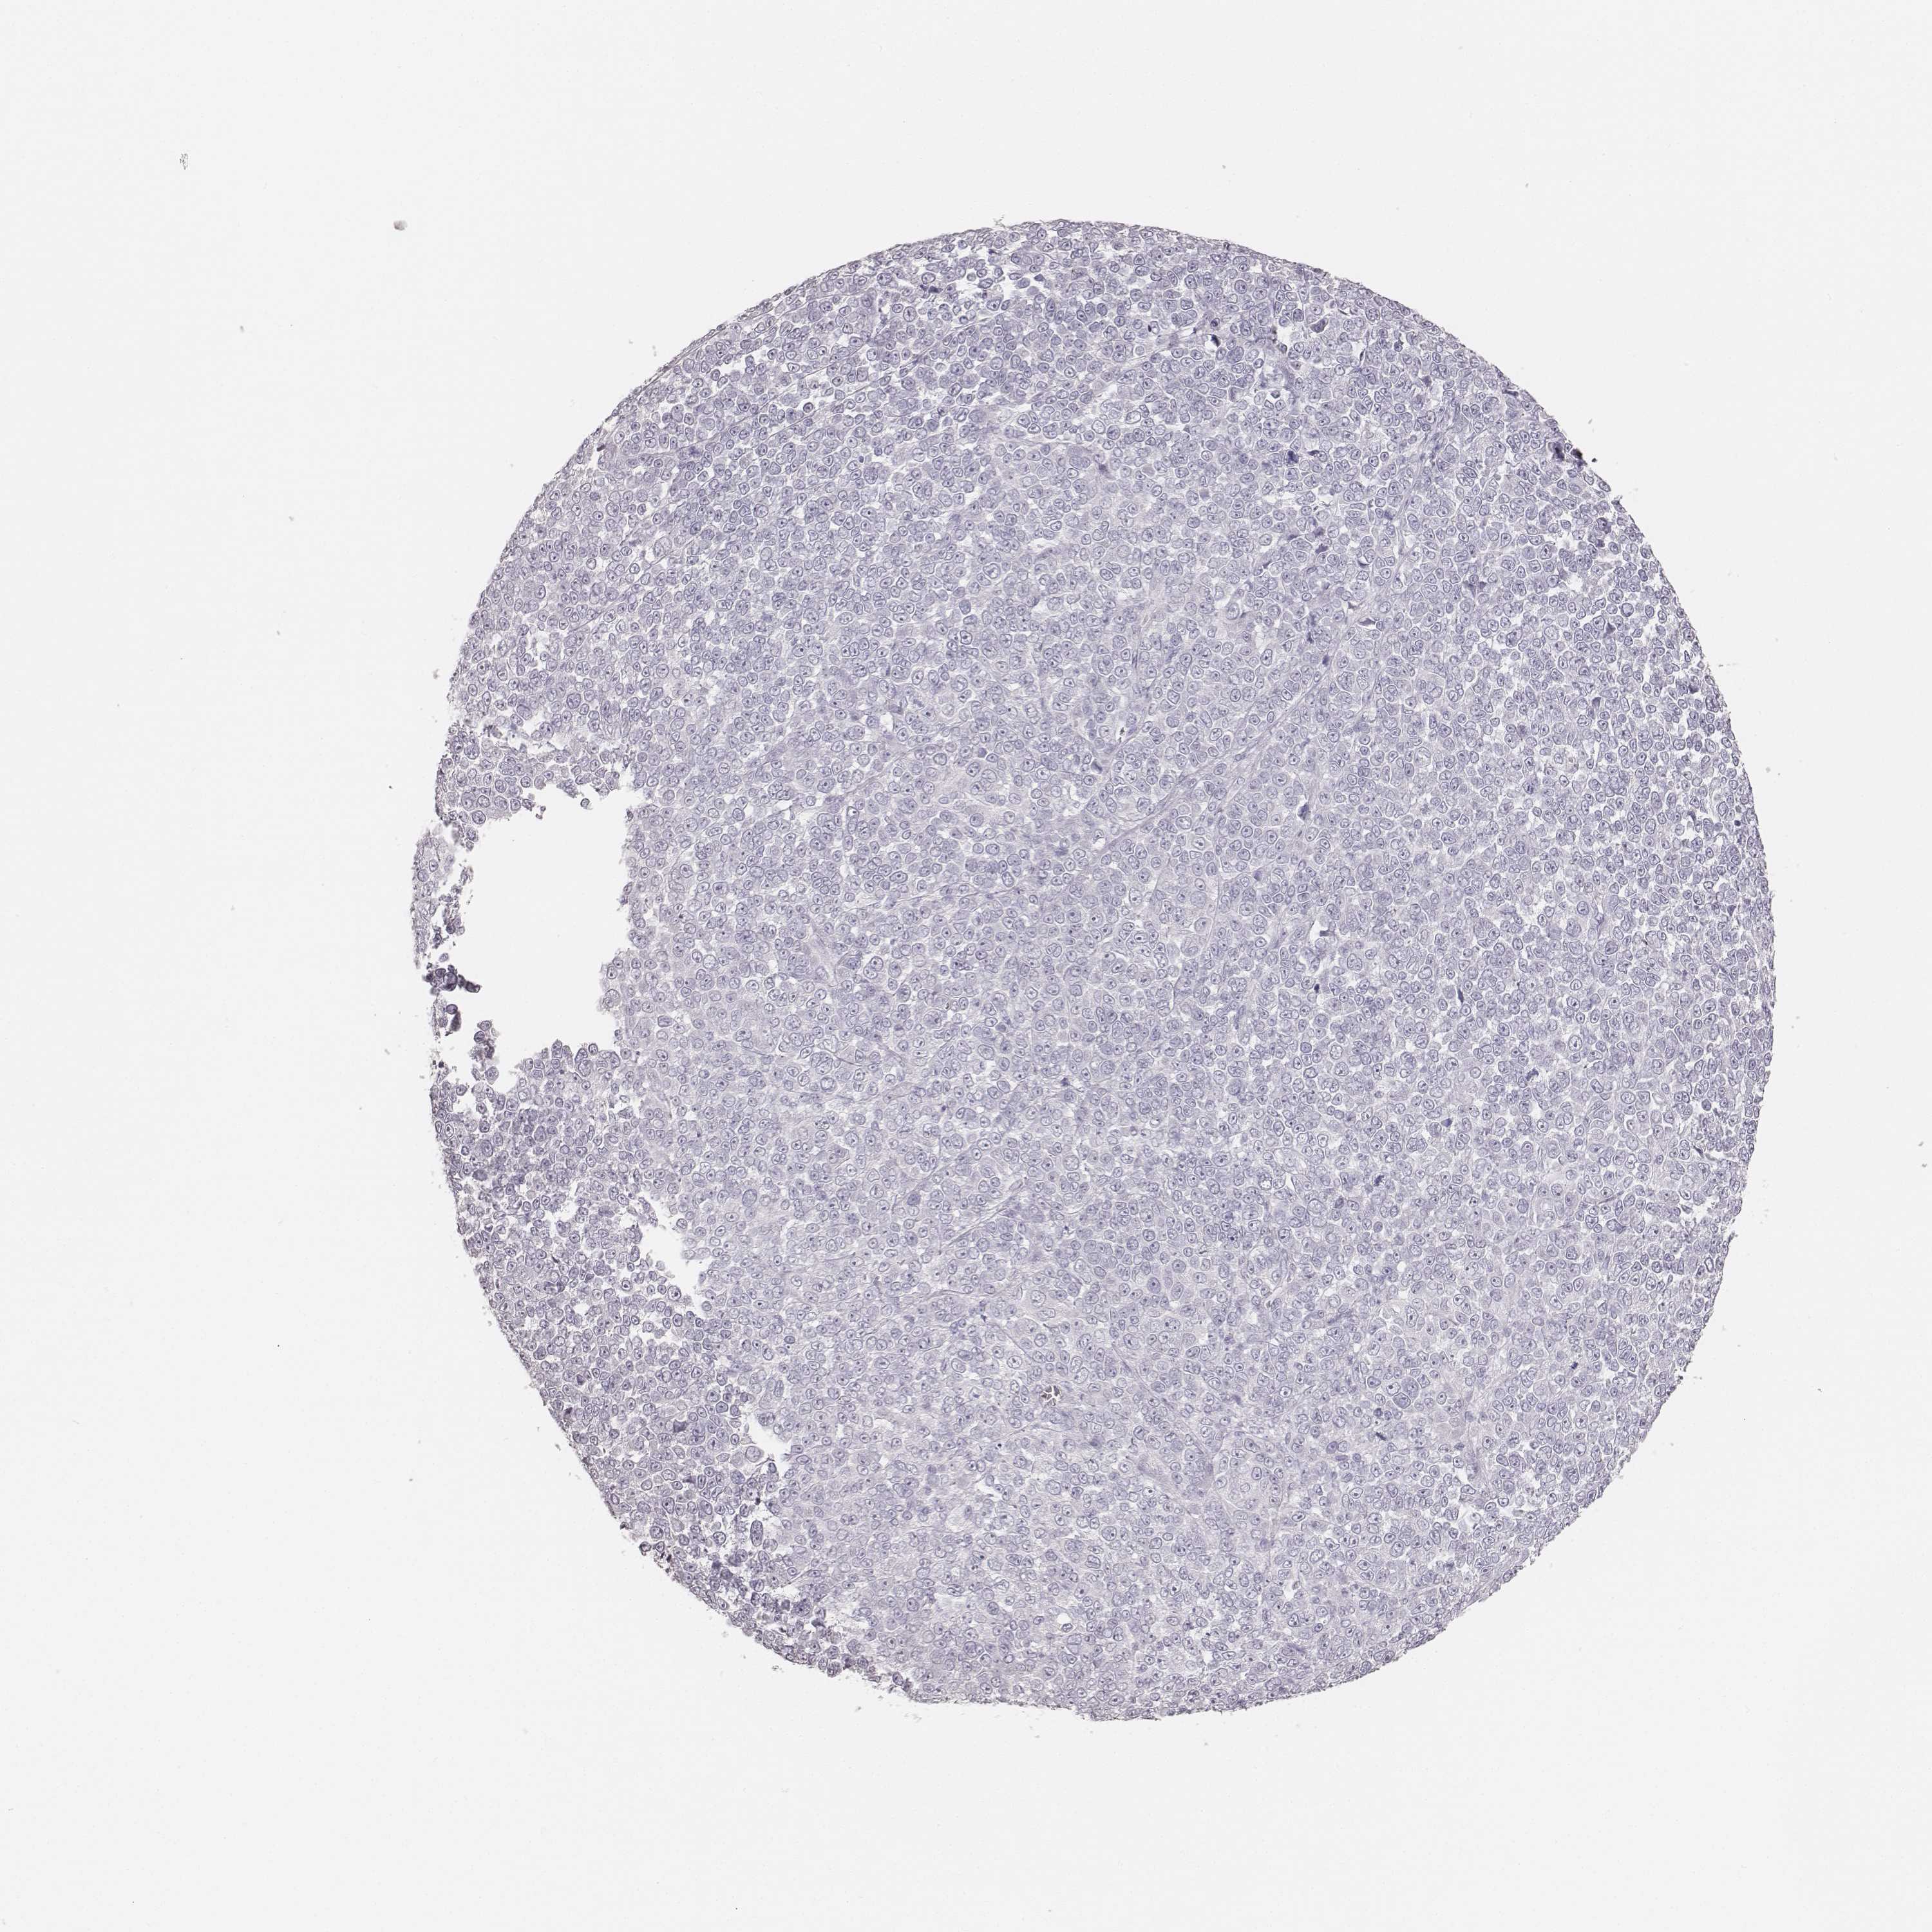

MELANOMA - Protein expressioni

A mouse-over function shows sample information and annotation data. Click on an image to view it in a full screen mode. Samples can be filtered based on level of antibody staining by selecting one or several of the following categories: high, medium, low and not detected. The assay and annotation is described here.

Note that samples used for immunohistochemistry by the Human Protein Atlas do not correspond to samples in the TCGA dataset.

Antibody stainingi

Antibody staining in the annotated cell types in the current human tissue is reported as not detected, low, medium, or high, based on conventional immunohistochemistry profiling in selected tissues. This score is based on the combination of the staining intensity and fraction of stained cells.

Each image is clickable and will lead to virtual microscopy that enables deeper exploration of all samples and also displays staining intensity scores, fraction scores and subcellular localization as well as patient and tissue information for each sample.

Antibody HPA055194

Antibody HPA072208

Staining

High

Medium

Low

Not detected

Intensity

Strong

Moderate

Weak

Negative

Quantity

>75%

75%-25%

<25%

None

Location

Nuclear

Cytoplasmic/membranous

Cytoplasmic/membranous,nuclear

Malignant melanoma, NOS

Malignant melanoma, Metastatic site